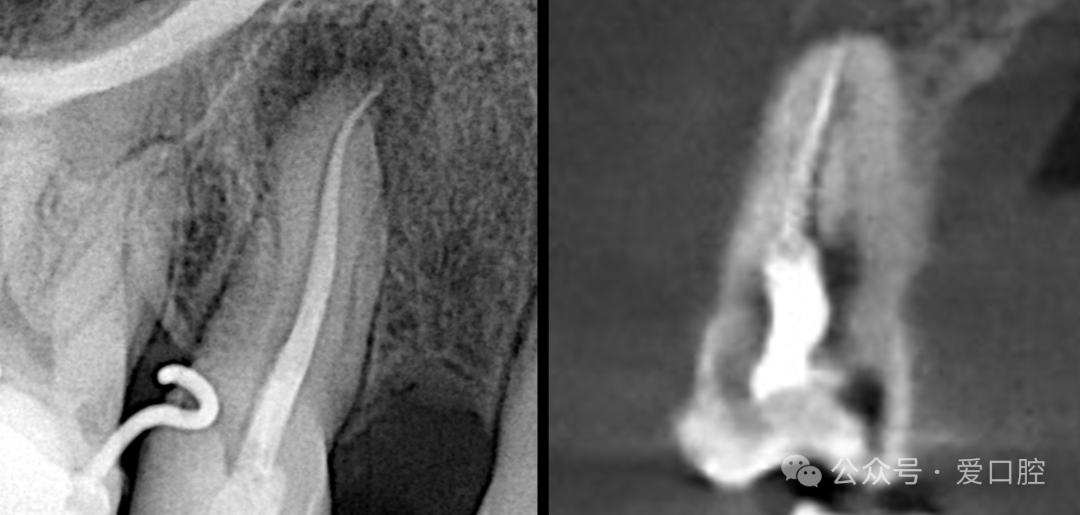

影像学检查:小牙片示:15冠部高密度影,根管内可见高密度影像,牙周膜增宽影,根尖低密度影。CBCT示:15遗漏腭侧根管。

15,安放橡皮障隔离后,显微镜下,开髓,暴露髓腔内牙胶,去除髓腔内牙胶,探查颊侧根管,使用再治疗镍钛锉去除根管上段牙胶,8号k锉,10号k锉疏通至根尖,3%次氯酸钠溶液冲洗,根测长度为19mm,3%次氯酸钠溶液冲洗,探查腭侧根管,发现髓室顶未揭干净,有牙胶残留,揭净髓室顶,去净残留牙胶,疏通腭侧根管至根尖,3%次氯酸钠溶液冲洗,根测长度为19mm,镍钛预备至3504,试尖, 3%次氯酸钠溶液冲洗, Eddy荡洗(20秒3次),蒸馏水冲洗,17%EDTA溶液冲洗,蒸馏水置换,吸干,氢氧化钙封药,玻璃离子暂封。